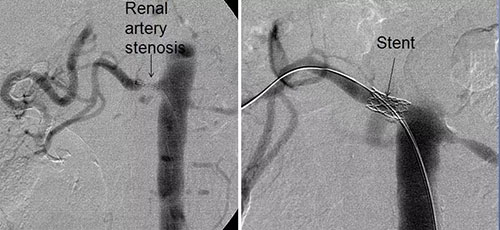

造影显示肾动脉重度狭窄

通过血管造影可进一步明确诊断,如发现重度狭窄,在导丝的导引下,一个微小的气囊在动脉的内部(腔)膨胀以扩张狭窄的动脉。

导丝通过病变,球囊扩张过程

此外,作为血管成形术流程的一部分,可将支架(用于防止狭窄复发的管状装置)置于动脉中。

肾动脉造影+支架植入术

支架植入后,肾动脉狭窄消失,肾脏的血流得到明显的改善,促使血压升高的激素分泌便减少了,血压也就低下来了。所以说如果您的高血压长时间难以控制,可以做个肾动脉彩超筛查一下,进行相应的治疗后,也许以后不用吃这么多,甚至不用吃降压药了。